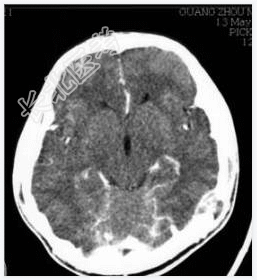

- [材料题] 病历摘要:男性,20岁。

主诉:发现头皮软组织肿物3个月。

现病史:三月前发现左枕部软组织轻微突起伴隐痛,到当地医院检查发现左枕部颅骨骨质缺损,未作具体治疗,现觉头皮肿物增大,时伴有气促、头痛。

专科检查:左颞枕部软组织略膨起,较软,各项病理反射(-)。